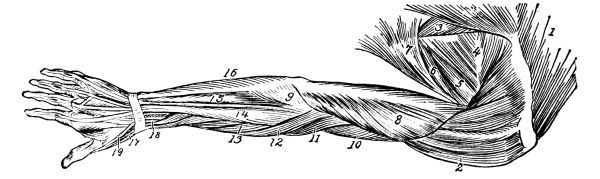

| The Upper Extremities | 171 |

The Shoulder Girdle, 171—The Clavicle, 171—The Scapula, 173—Shoulder Muscles, 174—The Humerus, 175—Upper Arm Muscles, 176—The Ulna, 177—The Radius, 178—The Wrist, 180—The Hand, 181—Meta-carpals, 181—Phalanges, 181—Muscles of the Forearm, 182—Muscles of the Hand, 184—Joints of the Upper Extremity, 185—Blood Supply of the Upper Extremity, 185—Nerves of the Upper Extremity, 186. |